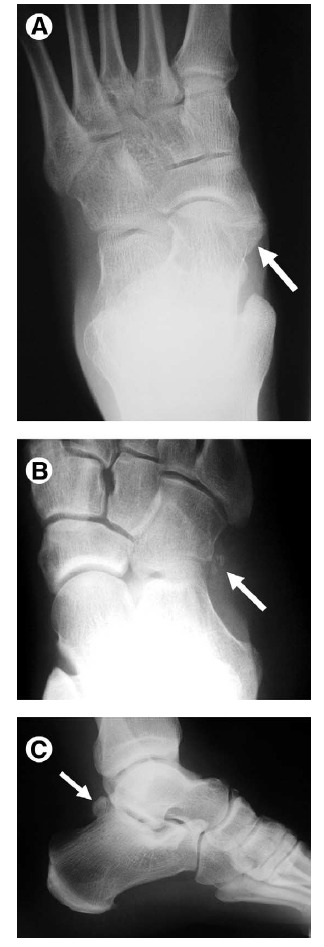

Figure 5 Fractures associated with ankle sprain. Avulsion fractures, particularly at the lateral malleolus, are common in the

setting of ankle sprain. Occasionally overlooked are sites of other fractures, including the following.

(A) Dorsal capsular avulsion. Lateral view of the foot demonstrates a curvilinear calcification dorsal to the talar head (arrow) representing a capsular avulsion. These may also occur at the navicular bone.

(B) Extensor digitorum brevis avulsion. Oblique view of the ankle shows thin calcification (arrow) adjacent to the anterolateral calcaneus consistent with an avulsion fracture from the origin of the extensor digitorum brevis tendon.

(C) Fifth metatarsal base fracture. AP view of the fifth metatarsal base in a skeletally immature patient shows a longitudinally directed, rounded ossification center (arrow) as well as a transversely directed avulsion-type fracture (arrowheads). Avulsion-type fractures in this location typically extend to the tarsometatarsal articular surface, whereas Jones-type fractures are more distal, occurring at the proximal shaft.